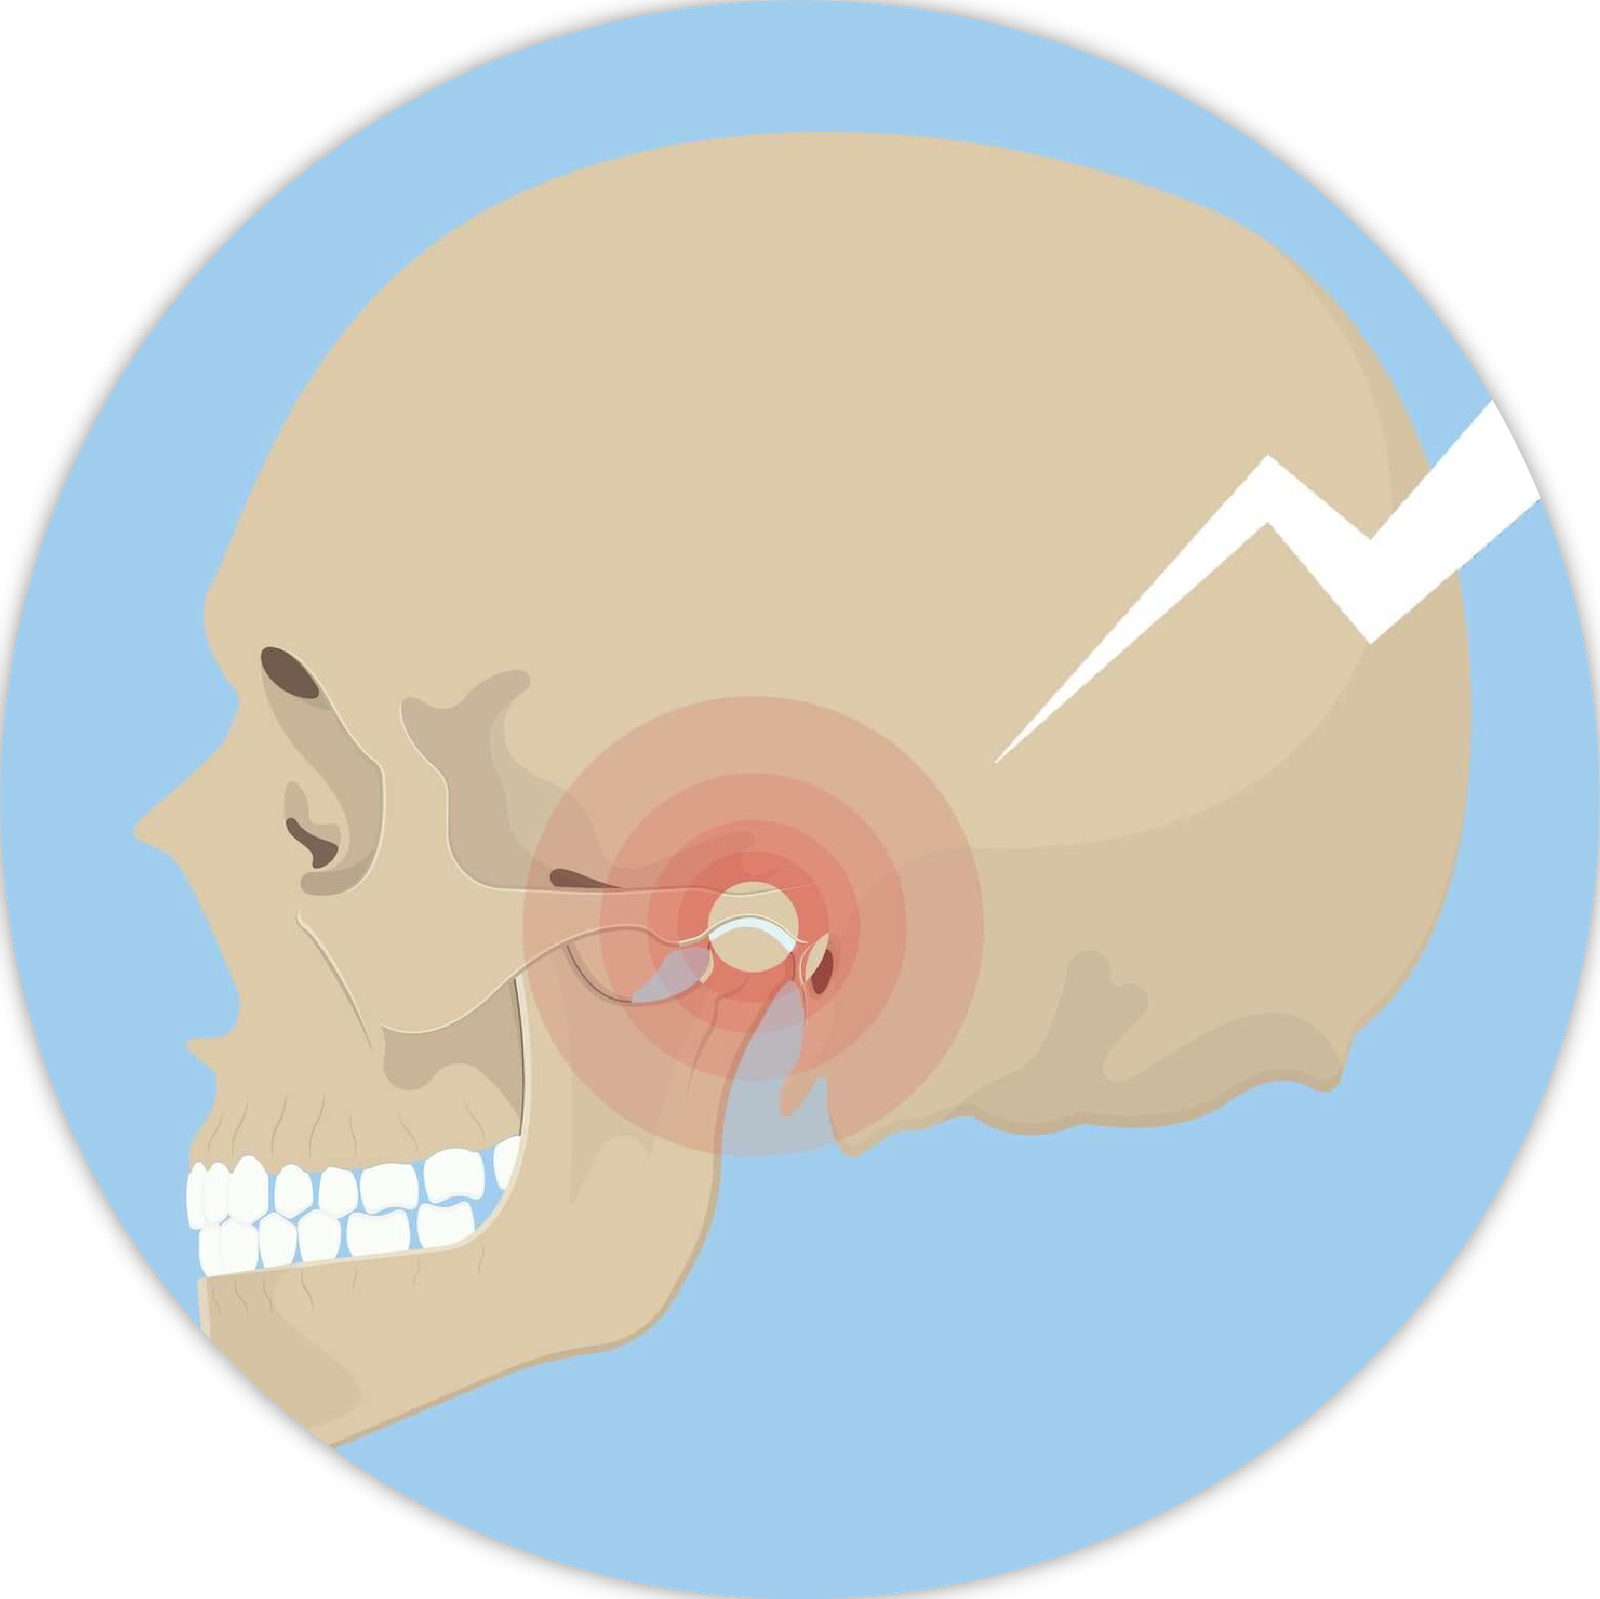

Răng khôn hay còn gọi là răng số 8, là những chiếc răng mọc ở phía trong cùng hai hàm răng ở những người trưởng thành trong độ tuổi trung bình từ 17- 25. Vì cấu trúc xương hàm người Việt chúng ta thường nhỏ, răng khôn không có đủ chỗ để mọc thẳng, dẫn đến tình trạng mọc lệch, mọc 1 phần, đâm xiên vào răng bên cạnh. Điều này dẫn đến nguy cơ kẹt thức ăn, viêm nướu, sâu răng, áp xe hoặc thậm chí là sưng viêm 1 bên mặt. Chúng tôi khuyến nghị khách hàng nên đi nhổ răng khôn từ giai đoạn răng mới mọc nhằm tránh các biến chứng và cơn đau.

Nhổ răng khôn luôn là nỗi lo âu và ám ảnh của nhiều khách hàng. Tuy nhiên, chúng tôi luôn đảm bảo gây tê – vô cảm vùng hoàn toàn để khách hàng không có cảm giác đau đớn trong quá trình nhổ răng. Quá trình nhổ răng khôn có thể kéo dài từ 10-30 phút tuỳ độ khó. Sau khi nhổ răng, có thể khách hàng sẽ thấy sưng nề, tình trạng này kéo dài khoảng 5-7 ngày. Bác sĩ sẽ cân nhắc tuỳ trường hợp cụ thể để kê toa thuốc sau điều trị nhằm giảm thiểu tối đa tình trạng sưng, đau, nhiễm trùng sau nhổ.